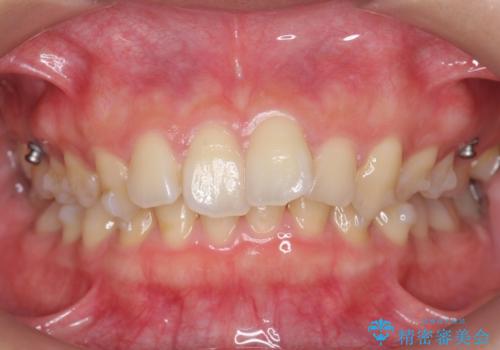

深いかみ合わせ 出っ歯の治療 インビザラインで

- 前歯の前突を主訴に来院。

かみ合わせが深く、また奥歯のかみ合わせも全体的に上が前にずれていました。

抜歯矯正も難しく、非抜歯矯正も歯の移動量が多くいずれにしても難易度が高い状態でした。

時間はかかりますが非抜歯で治療することにして、インビザライン矯正とワイヤー矯正を交互に行い仕上げました。

インビザライン矯正だけでなく、途中ワイヤー矯正もはさみました。前歯のかみ合わせが深く、本当に大変な治療でしたが協力度も高く非抜歯で上の奥歯を後ろに動かすことができました。